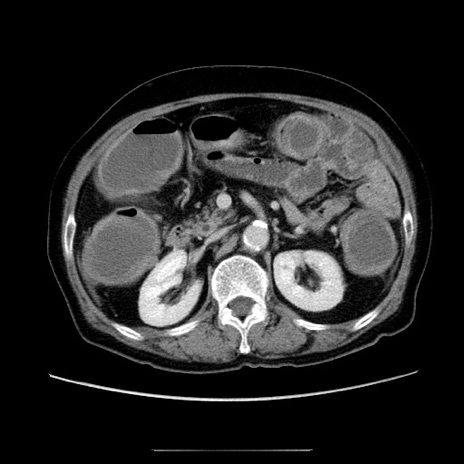

症例5(横断像)

【症例】70歳代女性

【主訴】お腹が張る

【現病歴】1週間くらい前から腹部膨満の自覚あり。昨日夜から増悪したため、本日救急外来受診。

【身体所見】意識清明、BT 36.5℃、BP 165/106mmHg、HR 80bpm、SpO2 98%、腹部:膨満、軟、自発痛・圧痛なし、触診にて不快感あり、腸蠕動音:減弱

【データ】WBC 12600、CRP 1.04